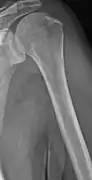

The diagnostic examination of a person with suspected multiple myeloma typically includes a skeletal survey. This is a series of X-rays of the skull, axial skeleton, and proximal long bones. Myeloma activity sometimes appears as "lytic lesions" (with local disappearance of normal bone due to resorption) or as "punched-out lesions" on the skull X-ray ("raindrop skull"). Lesions may also be sclerotic, which is seen as radiodense.[70] Overall, the radiodensity of myeloma is between −30 and 120 Hounsfield units (HU).[71] Magnetic resonance imaging is more sensitive than simple X-rays in the detection of lytic lesions, and may supersede a skeletal survey, especially when vertebral disease is suspected. Occasionally, a CT scan is performed to measure the size of soft-tissue plasmacytomas. Nuclear Medicine Bone scans are typically not of any additional value in the workup of people with myeloma (no new bone formation; lytic lesions not well visualized on nuclear bone scan).

Multiple myeloma in the upper arm

Humerus with multiple myeloma lesions